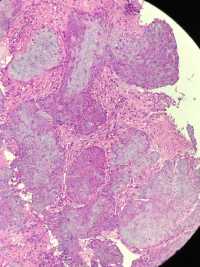

最近一段时间活检组织,染色苍白,尤其是胃肠食管,肿瘤细胞都白的不能看,请教一下这是什么原因,别的都可以,就活检的不行,排除了脱水及脱蜡

图1

图2

图3

图4